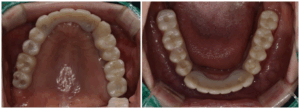

상, 하악 모두 디지털 풀아치 임플란트로

진행을 하였는데요.

디지털 풀아치 임플란트는 평균 4~6개의

임플란트를 식립하여 하나의 보철물로 연결해

치아의 기능과 심미성을 회복시켜주는 시.술을 말합니다.

디지털 풀아치는 자연치의 기능을 80~90%까지

회복시켜주는 장점이 있습니다.

게다가 시술 당일에 임시 보철물 체결이

가능하기 때문에 기존 임플란트 보다

일상으로 복귀가 더욱 빨라집니다.